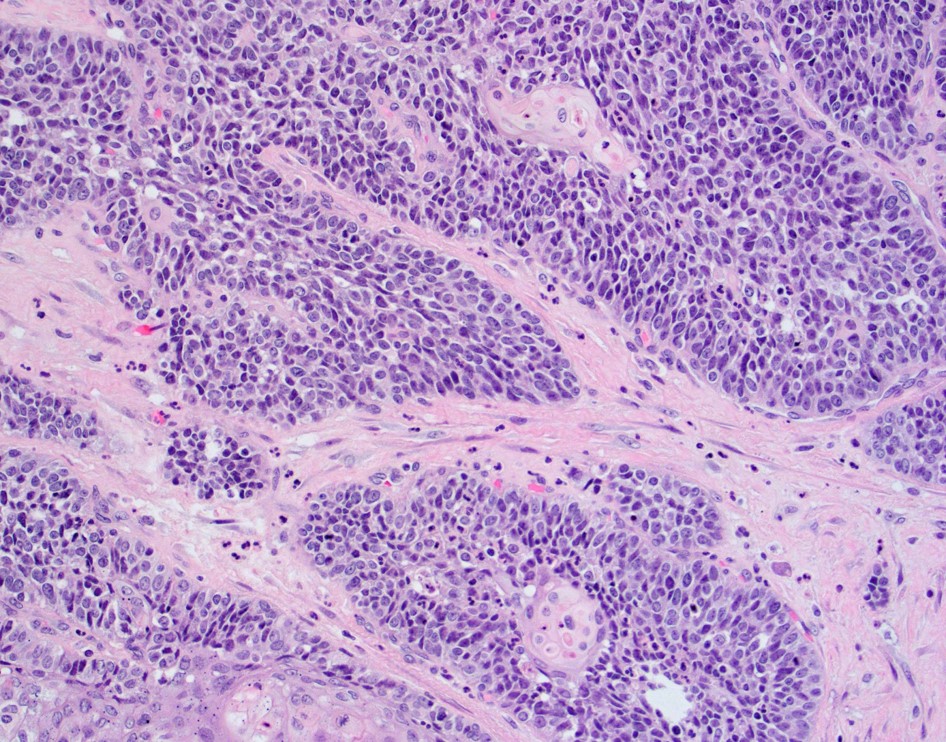

40 year old female with pelvic mass and friable cervix, biopsy was performed at OSH....